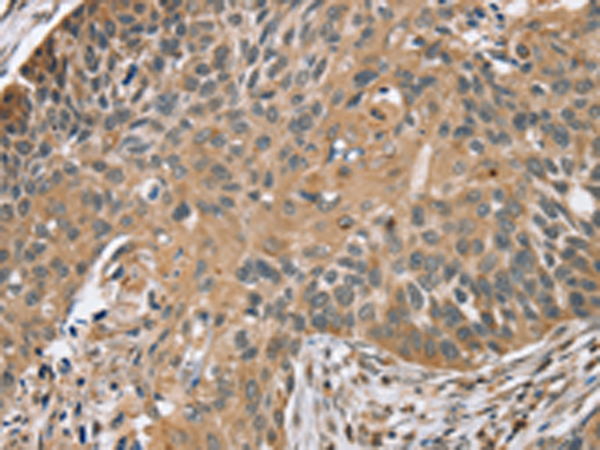

分类: 科研抗体货号: P05259别名: RPSKA; NY-CO-10; SDCCAG10; SDCCAG-10应用: WB,IHC反应种属: Human, Mouse, Rat